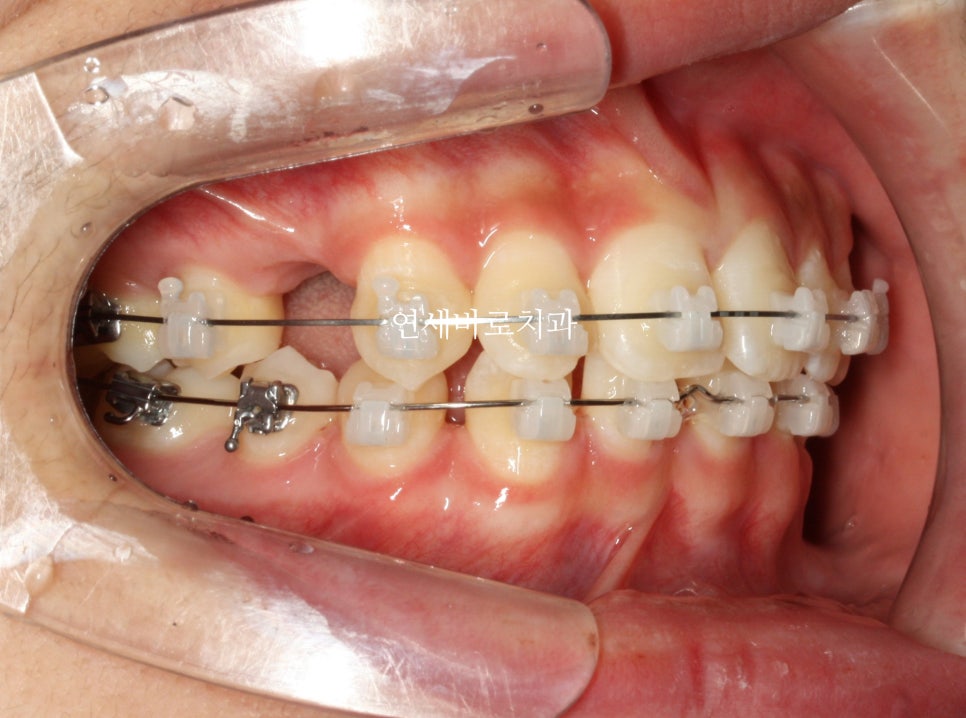

이 친구는 약간의 돌출도 보이고 있었기 때문에 위쪽 치아를 두개 발치했었습니다.

약2년의 치료기간이 걸렸으며 올해 초에 정기검진을 왔습니다

치료가 끝난지 약 3년정도 지난 모습인데 긴밀한 교합으로 인해 치료결과가 잘 유지되고 있는 것 같습니다.